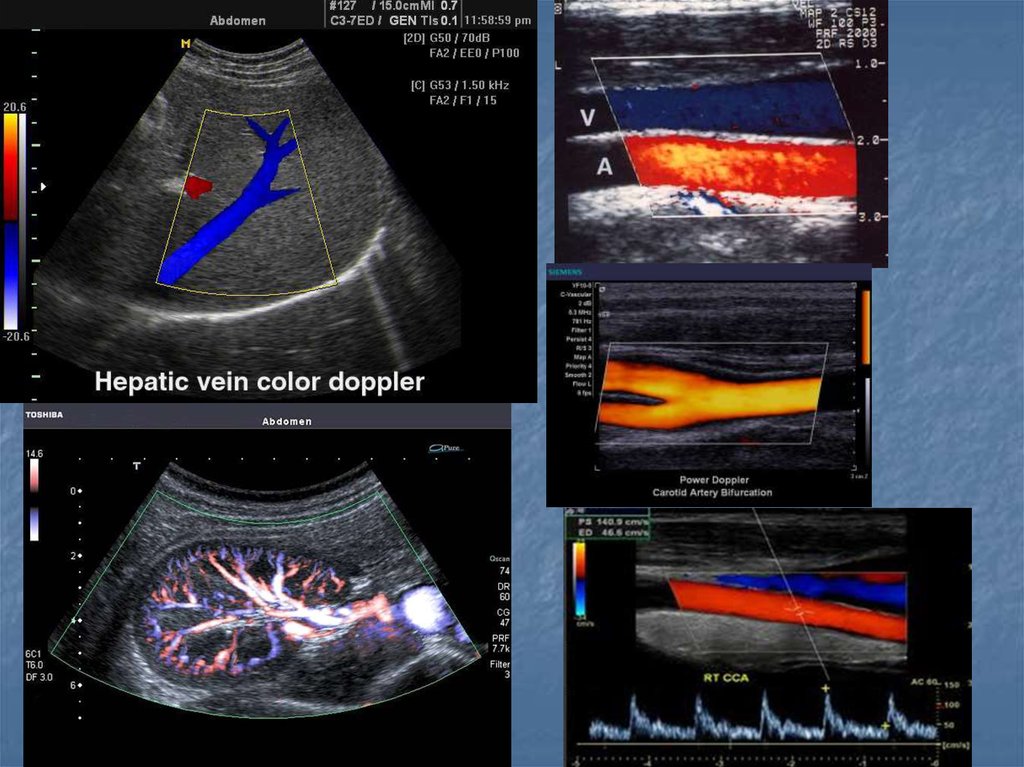

36. Показания

Воспалительные заболевания брюшной полости,

малого таза и шеи…

Наличие жидкости в брюшной и грудной полостях, в

суставах

Визуализация мягких тканей(мышцы, связки,

околосуставные пространства)

Желчекаменная, почечнокаменная болезни

Диагностика опухолей (молочная железа, яичники,

лимфоузлы)

Заболевания сосудов(варикозная болезнь,

эндортереит, оартиты, аневризмы, ангиопатия)

Врожденные и воспалительные заболевания

сердца(пороки клапанного аппарата, дефекты

стенок, нарушение функции миокарда, эндокардит,

перикардит)